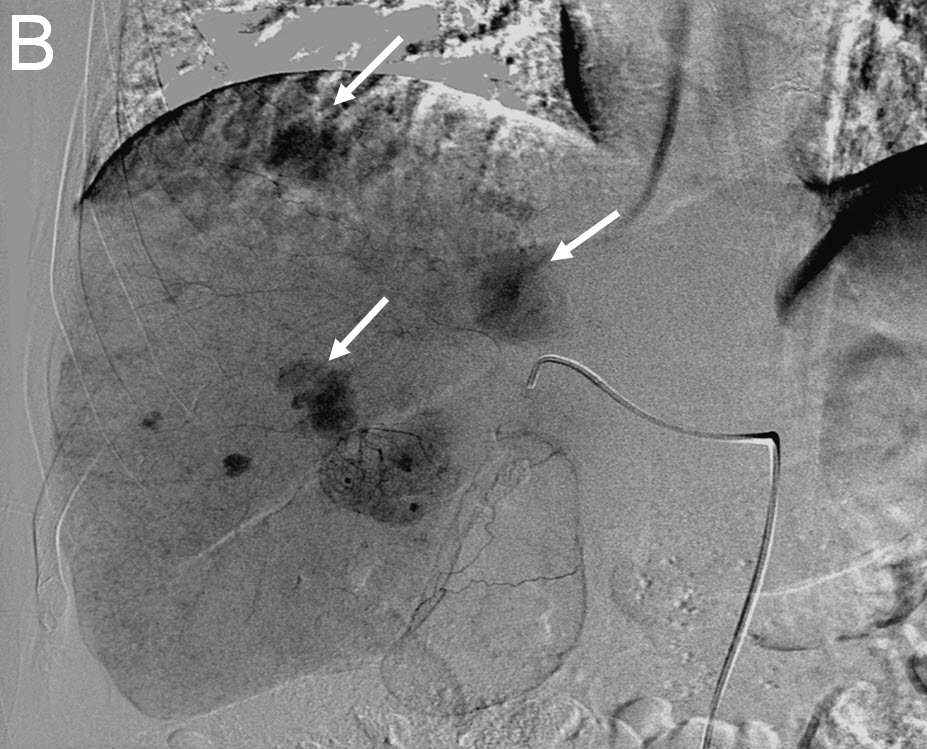

Treating Multiple Liver Tumors with Drug Eluting Beads (DEB TACE)

|

| (B) Delayed right liver angiogram showing multiple tumor "blushes" |